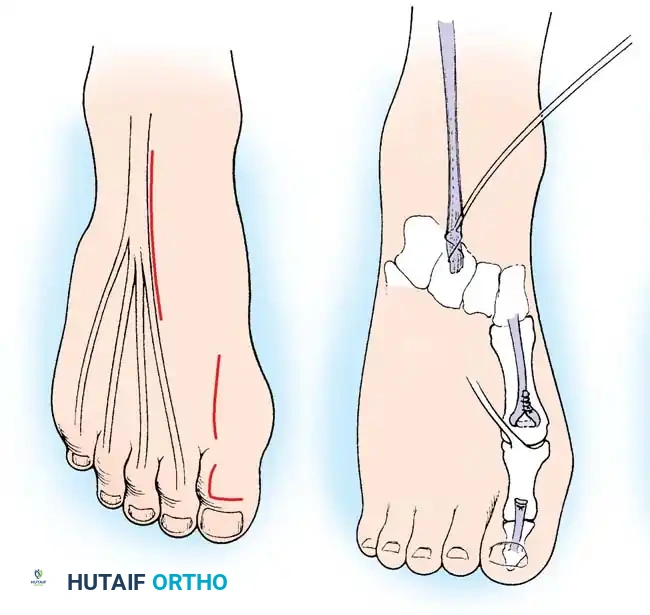

Fig. 32-23 Transfer of extensor hallucis longus tendon for claw toe deformity (Jones procedure). A, Incisions. B, Completed procedure with IP joint fusion.

Surgical Steps:

1. Exposure: Expose the interphalangeal (IP) joint of the great toe through an L-shaped or dorsal longitudinal incision.

2. Tendon Harvest: Isolate the Extensor Hallucis Longus (EHL) tendon. Transect it just proximal to its insertion at the base of the distal phalanx.

3. IP Joint Fusion: To prevent the development of a severe hallux malleus (drop toe) post-transfer, the IP joint must be arthrodesed. Denude the articular cartilage of the IP joint and fix it with a longitudinal K-wire or a headless compression screw.

4. Tendon Routing: Make a second incision over the neck of the first metatarsal. Retrieve the EHL tendon proximally into this wound.

5. Fixation: Drill a transverse hole through the neck of the first metatarsal. Pass the EHL tendon through the bone tunnel and suture it back onto itself under physiological tension with the ankle held in neutral dorsiflexion.